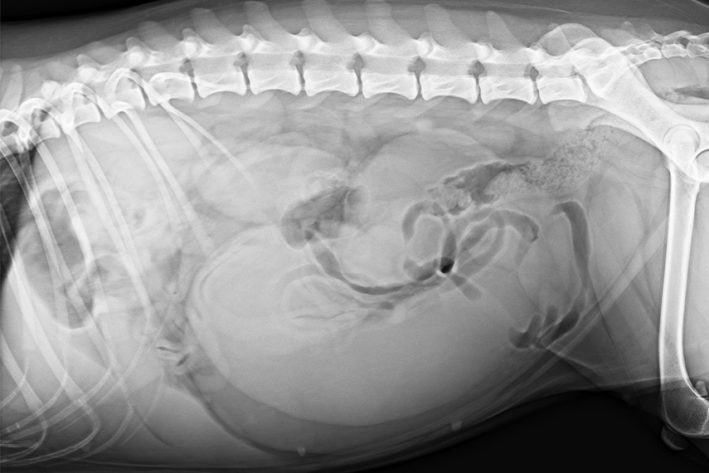

Pyometra: Röntgenbilder können bei der Diagnose hilfreich sein

Röntgenbilder können bei der Diagnose hilfreich sein

Pyometra Roentgen

Bei Tieren mit den oben angeführten Symptomen und Verdacht auf eine Pyometra wird eine komplette Abklärung angeraten. Diese beinhaltet die klinische Untersuchung und ein großes Blutbild inklusive Organwerte. Zur genaueren Lokalisation des Problems dient die Ultraschalluntersuchung der Bauchhöhle. Gegebenenfalls kann auch eine Röntgenuntersuchung durchgeführt werden. Der Vaginalausfluss kann unter dem Mikroskop genauer untersucht werden. Eine steril entnommene Gebärmutterflüssigkeit kann postoperativ für die bakteriologische Untersuchung eingeschickt werden.